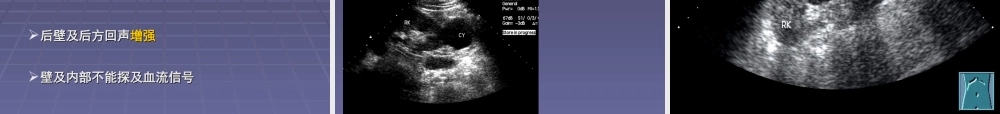

泌尿系统超声检查泌尿系统超声检查泌尿系统超声检查泌尿系统超声检查重庆医科大学第一附属医院超声科重庆医科大学第一附属医院超声科李玲李玲重庆医科大学第一附属医院超声科重庆医科大学第一附属医院超声科李玲李玲肾脏解剖概要肾脏解剖概要肾门肾窦实质皮质髓质输尿管肾脏正常声像图肾脏正常声像图包膜包膜::光滑的光滑的线状强回声线状强回声实质实质::肾周边的中低回声肾周边的中低回声窦区窦区::肾中心光点粗大的高回声肾中心光点粗大的高回声长100~120mm宽50~60mm厚30~40mm肾脏常见病超声表现肾脏常见病超声表现肾脏常见病超声表现肾脏常见病超声表现肾积水(肾积水(nephrohydrosis)nephrohydrosis)病理病理::肾积水是指因尿路梗阻而引起的肾盂和肾积水是指因尿路梗阻而引起的肾盂和//或肾盏扩张或肾盏扩张临床表现临床表现:慢性肾积水多表现为患侧腰部胀痛,:慢性肾积水多表现为患侧腰部胀痛,急性肾积水常表现为患侧腰部或下腹部剧烈绞急性肾积水常表现为患侧腰部或下腹部剧烈绞痛伴血尿痛伴血尿超声表现超声表现肾窦肾窦光点光点分离分离,为大小及形态不一的,为大小及形态不一的无回声占据无回声占据彩色多普勒显像:彩色多普勒显像:无回声内不能探及血流信号无回声内不能探及血流信号重度积水时常有肾脏增大,肾实质变薄重度积水时常有肾脏增大,肾实质变薄可伴同侧输尿管积水可伴同侧输尿管积水肾结石(肾结石(nephrolith)nephrolith)临床表现临床表现:肾结石临床上多无症状,结石较多或伴肾:肾结石临床上多无症状,结石较多或伴肾积水时可有患侧腰部胀痛积水时可有患侧腰部胀痛超声表现超声表现::11、、肾窦区内肾窦区内一枚或多枚大小不等的一枚或多枚大小不等的强回声团强回声团,其后,其后伴有伴有声影声影22、可伴局限性肾积水、可伴局限性肾积水肾占位性病变肾占位性病变囊性囊性囊肿,多囊肾囊肿,多囊肾实性实性良性良性::错构瘤错构瘤恶性恶性::肾细胞癌,肾恶性淋巴瘤,肾母细胞瘤肾细胞癌,肾恶性淋巴瘤,肾母细胞瘤肾囊肿(肾囊肿(renalcyst)renalcyst)病理病理:发病机理不清,可能与老年退行性变有关,:发病机理不清,可能与老年退行性变有关,囊壁由具分泌功能的上皮细胞构成,内为澄清囊壁由具分泌功能的上皮细胞构成,内为澄清液体液体临床表现临床表现:多无临床症状,较大时可有患侧腰部:多无临床症状,较大时可有患侧腰部酸胀不适酸胀不适超声表现超声表现实质内实质内...